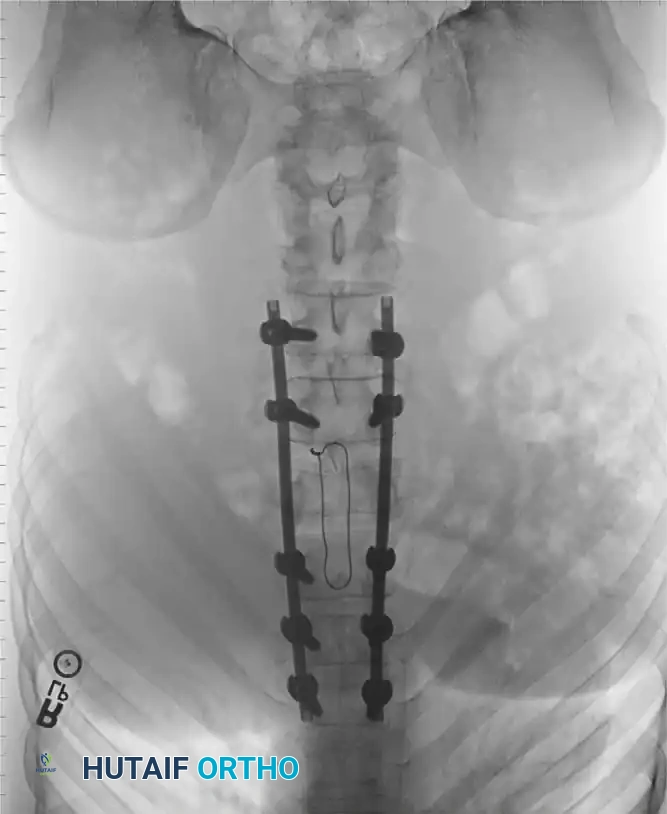

Depending on the fracture morphology, surgeons may employ posterior pedicle screw constructs, anterior plating, or a combined 360-degree approach.

The patient is positioned prone on a radiolucent Jackson table. Neuromonitoring (SSEPs and MEPs) is established. A standard midline posterior approach is utilized, carefully preserving the facet capsules of adjacent uninjured levels.

Pedicle screws are inserted under fluoroscopic or navigation guidance. The trajectory must respect the anatomical convergence of the pedicles, which varies from the thoracic to the lumbar spine.

Following screw placement, rods are contoured to restore physiological sagittal alignment (thoracic kyphosis or lumbar lordosis). Distraction or compression forces are applied based on the fracture pattern (e.g., compression for tension-band failures, distraction for burst fractures undergoing ligamentotaxis).

Associated Surgical & Radiographic Imaging